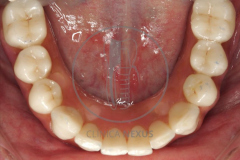

Rehabilitación bimaxilar fija implanto-soportada mediante un enfoque novedoso que se argumenta bajo el uso de nuevos materiales restauradores. Se trata de un paciente que era portador de una rehabilitación sobre implantes previa fracasada. Si desea conocer en detalle las características del caso clínico puede acceder al artículo que publicamos al respecto en el Journal Prosthetic Dentistry